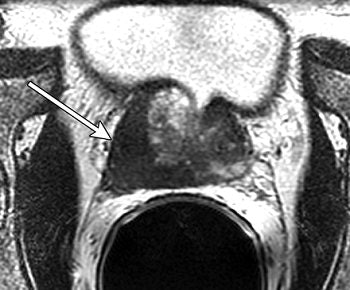

| Unenhanced T2-weighted fast spin-echo (5000/96 [effective]) endorectal coil pelvic MR images in 61-year-old man with clinical stage T2a prostate cancer. Transverse image shows a dominant tumor (arrow) at the right base; loss of normal contour and irregular bulging are evidence of extracapsular disease. Figure 8a. Hricak H, Choyke PL, Eberhardt SC, et al. "Imaging Prostate Cancer: A Multidisciplinary Perspective," Radiology 2007;243:28-53. |